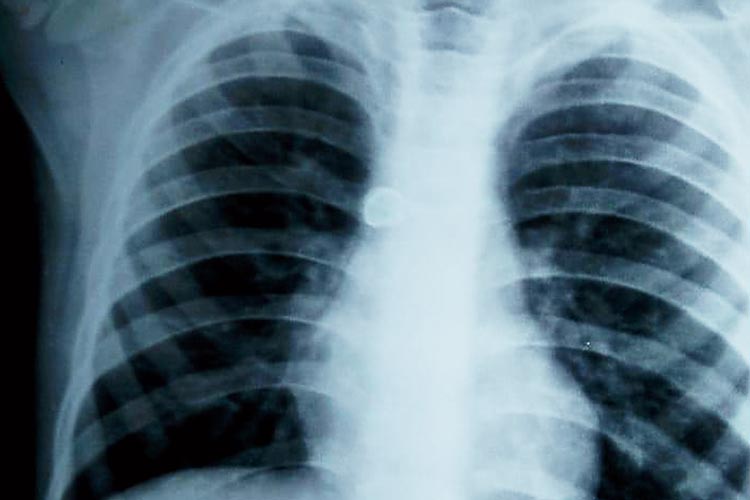

এক্স-রে প্লেটে স্পষ্ট, তখনও আটকে রয়েছে স্টিলের ক্রাউন (চিহ্নিত)। নিজস্ব চিত্র

সাগর দত্ত হাসপাতাল সূত্রে জানা গিয়েছে, এক্স-রে এবং প্রয়োজনীয় অন্য পরীক্ষা করে চিকিৎসকেরা দেখেন, শ্বাসনালীতে ওই স্টিলের ক্রাউনই আটকে রয়েছে। অস্ত্রোপচার করে সেটা বের করতে হবে বলেও তাঁরা পরিবারকে জানিয়েছিলেন। তবে সেই পরিকাঠামো সাগর দত্ত মেডিক্যাল কলেজ হাসপাতালে নেই। তাই তিন বছরের শিশুকে নিয়ে দ্রুত এসএসকেএম হাসপাতালে নিয়ে যাওয়ার পরামর্শ দেওয়া হয়।